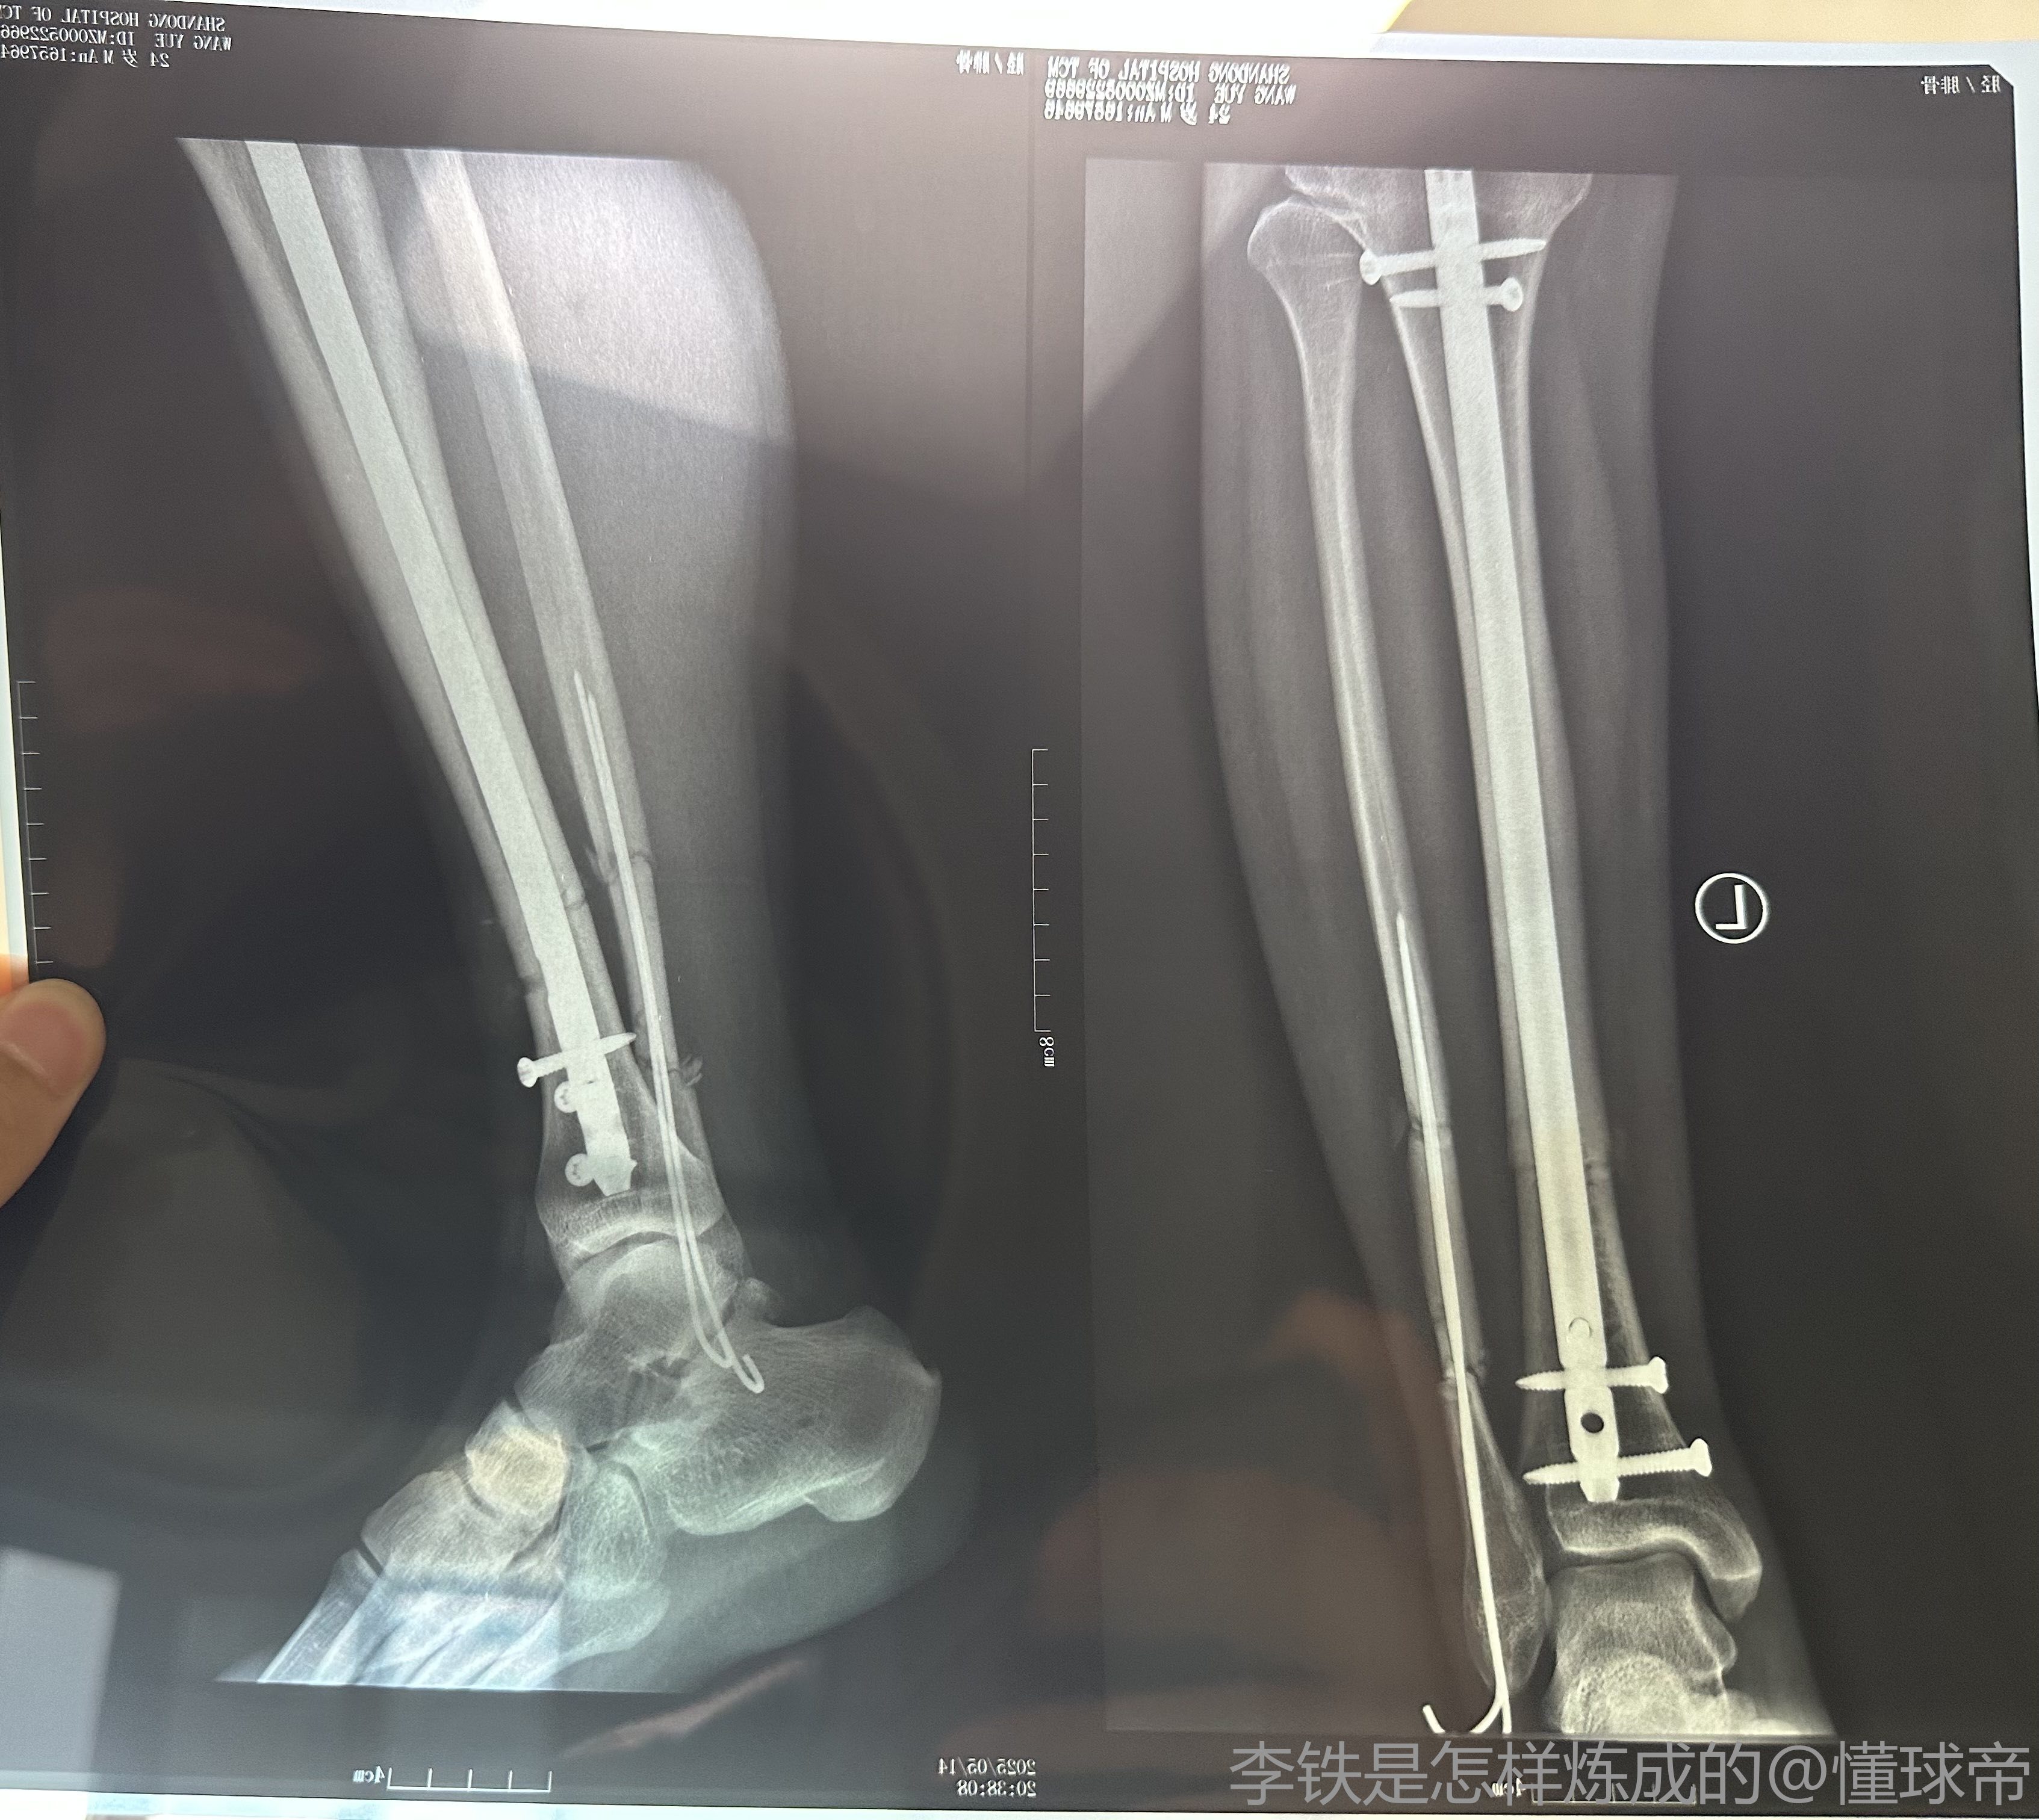

据记者牛志明的消息,山东泰山B队中场艾孜海尔初步诊断为右胫腓骨中段骨折。

牛志明写道:在昨晚山东泰山B队对阵兰州比赛中受伤的艾孜海尔,初步诊断是右胫腓骨中段骨折,今天等专家会诊后确定治疗方案。泰山队会给他提供最好的治疗和康复支持,祝福小伙子早日康复。

去年4月份踢球也是胫腓骨中段骨折,当时的场景至今忘不了,所以球员的心理创伤永远大于身体上的创伤,但好在现在医疗手段十分发达,这种的骨折在医院里都有微创做饭,我是4个月就可以下地走路,我的主治医师是给张驰做手术的医生,如果手术完成后接受专业的康复训练,4个月就能接受低强度的训练,但是会有一根长的钢钉留在腿里,不耽误正常的运动,张驰在青岛踢的那一年腿里就一直有,等着以后可以在拆出来,其实在某种意义上骨头断了也是一种好事,因为骨头是可以百分百痊愈的,但韧带肌肉不可以,还是那句话,康复后球员需要很长的时间走出心理阴影,能做到和张驰一样就非常厉害了,最后祝小艾早日康复,走出心魔